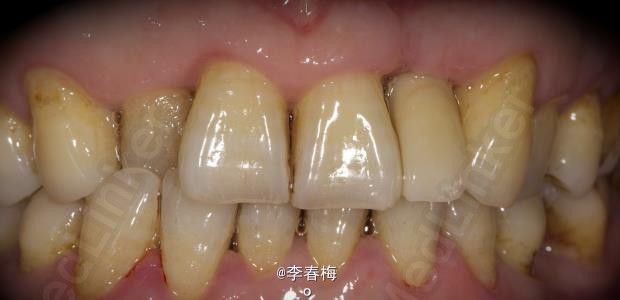

上颌前牙种植修复

患者,男,左上颌侧切牙缺失来诊。平素体质一般,无药物、食物过敏史,无高血压、心脏病等系统性疾病。

效果很好,患者满意